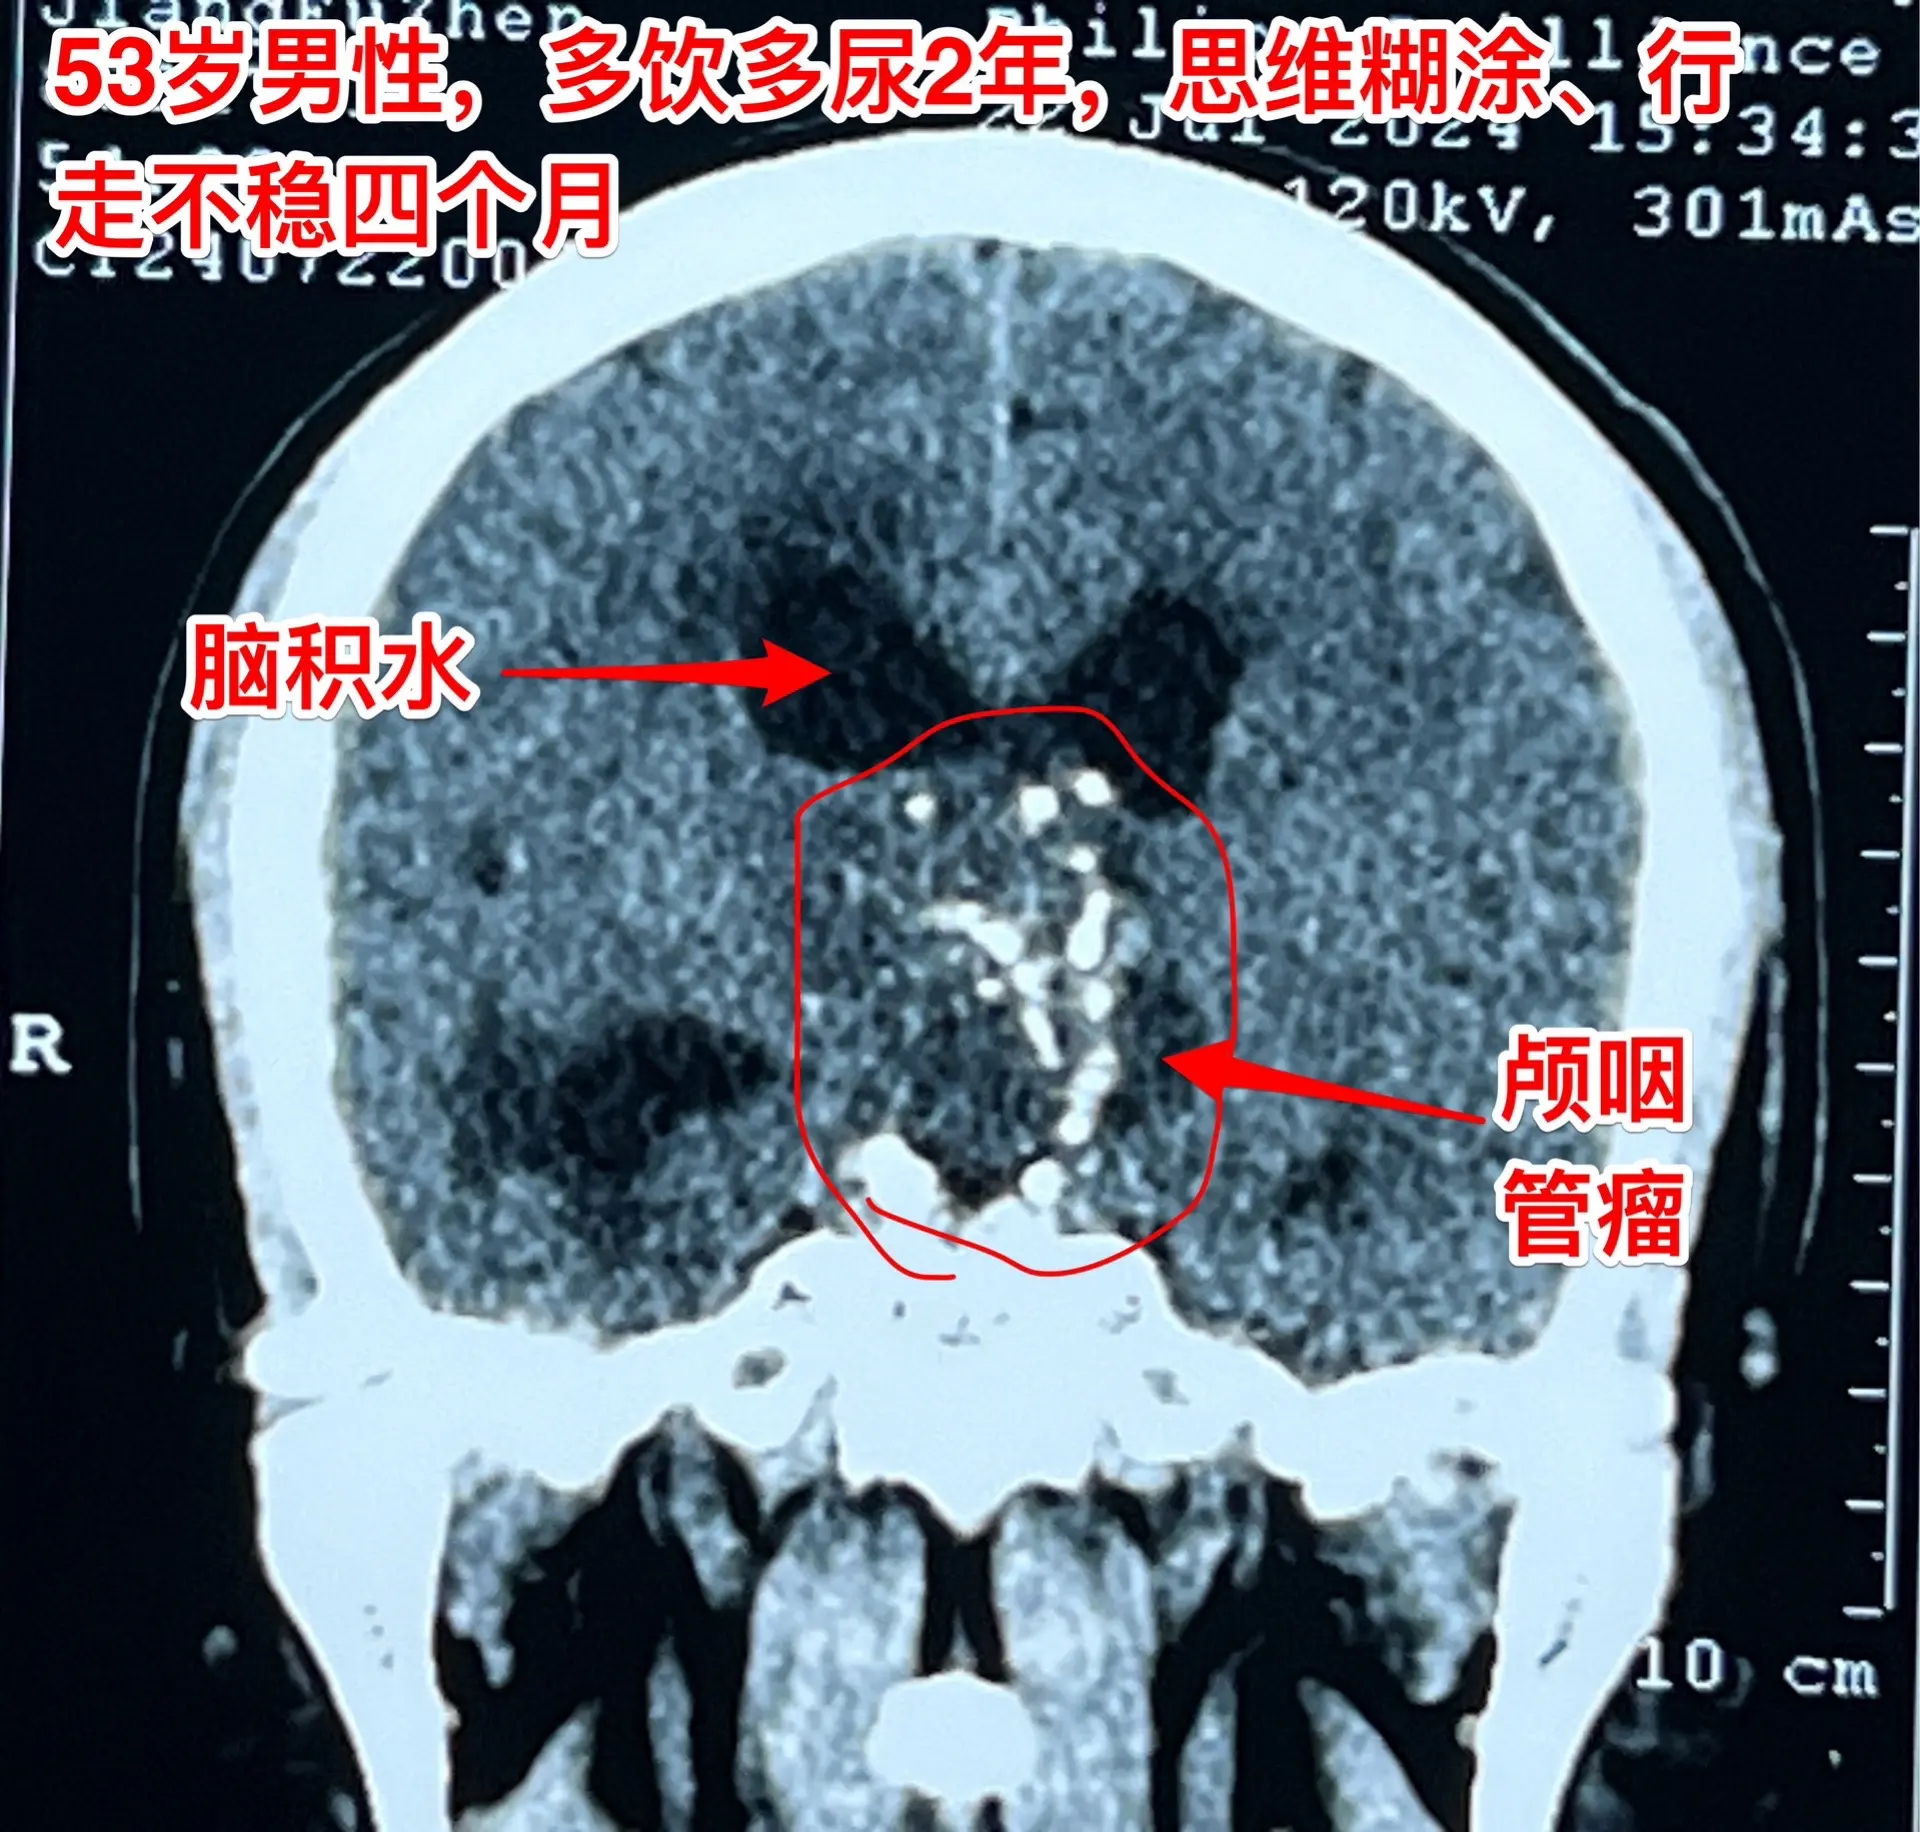

到医院作脑部磁共振检查,发现了脑部长了一个大肿瘤-颅咽管瘤,伴有脑积水。这个肿瘤直径接近5厘米,几乎是实性肿瘤,有很多的钙化斑,见图

思维糊涂、行走不稳、尿失禁这三个症状都是脑积水造成的。

而脑积水是颅咽管瘤堵塞脑室系统造成的。